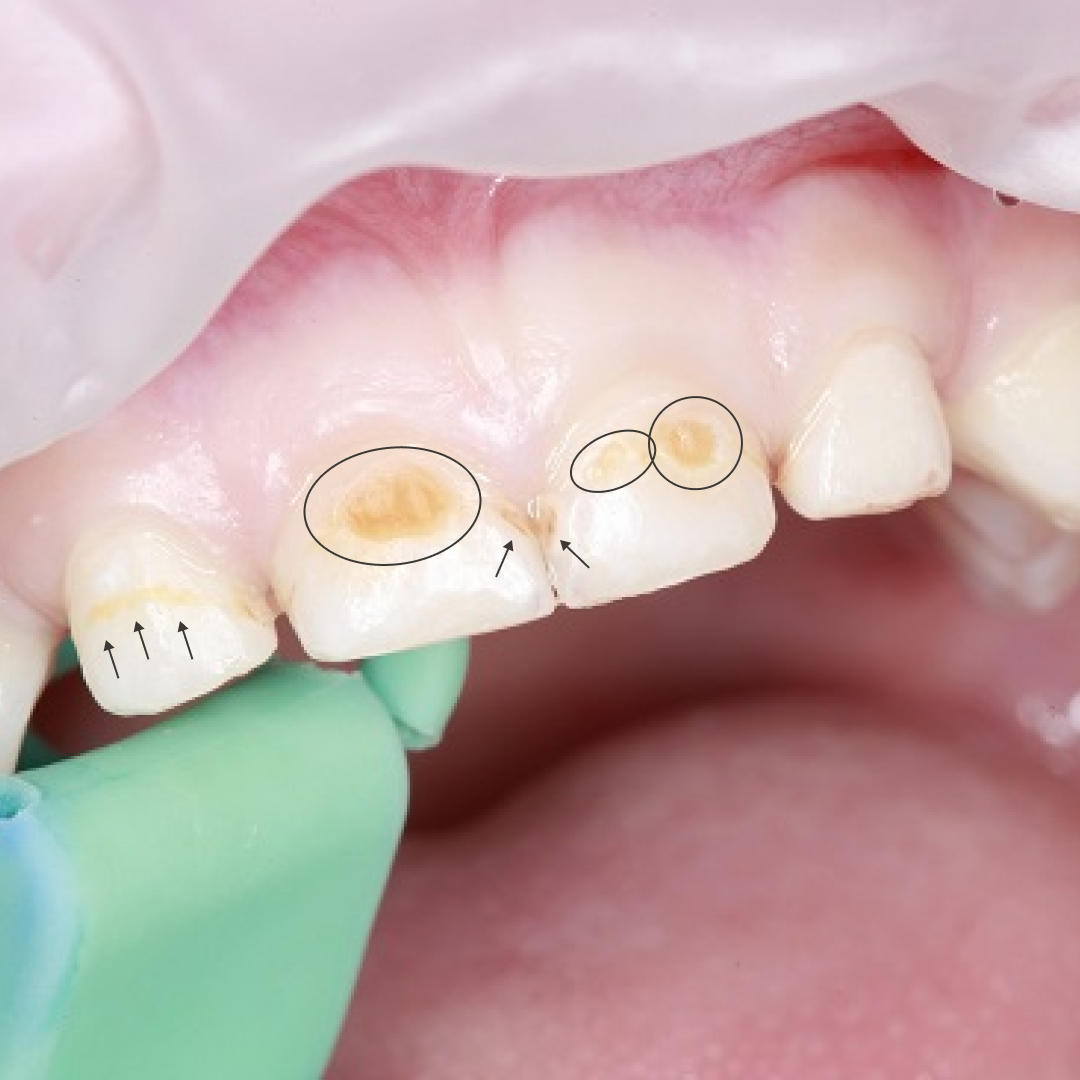

Бывают случаи, когда у ребенка не так много зубов, но они уже все желтовато-коричневые, с неровностями и полостями или покрыты белыми матовыми пятнами. Возможно, подобная проблема имеется и у Вашего ребенка. Если это так, необходимо срочно обратиться к врачу! Высока вероятность того, что это «бутылочный» кариес

"Бутылочный" кариес

Основная причина «бутылочного» кариеса – привычка давать ребенку перед сном и во время сна:

Во время сна выделение слюны замедляется и естественный процесс самоочищения зубов практически не происходит - любой налет и остатки пищи становятся причиной размножения болезнетворных микроорганизмов и разрушения неокрепшей эмали